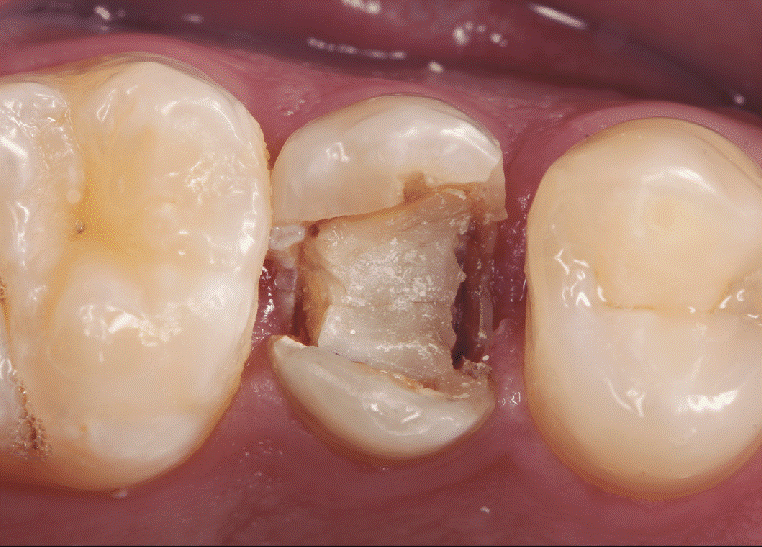

5) شکستن یا ترک دندان

این مشکل اولین نوع آسیب ها و جراحات متداول دهان و دندان است. یک اتفاق ممکن است موجب شکسته شدن دندان شما شود. برای مثال یک مسئله ناچیز مانند رفتن یک پاپ کورن سفت زیر دندان شما، ممکن است موجب آسیب رسیدن به دندان و شکسته شدن آن شود. اگر شکستگی تاج دندان شما زیاد باشد، دندانپزشک میتواند با استفاده از یک ماده رزینی قوی، بخش شکسته شده را جایگزین و ترمیم کند. اما اگر شکستگی در ناحیه پالپ رخ داده باشد، ممکن است دندان شما نیاز به عصبکشی پیدا کرده و باید حتماً پس از آن روکش شود.

ممکن است در اثر اتفاقاتی ساده مانند فوتبال بازی کردن و یا انجام سایر ورزش ها بدون محافظ دندان، جویدن غذای سفت، تصادف و یا هر چیز ساده دیگری یکی یا چند تا از دندان های شما ترک بخورد. آیا دندانپزشک می تواند دندان شما را حفظ و ترمیم کند و یا باید آن را بکشید؟ این امر به شدت ترک خوردگی دندان شما وابسته است. بیشتر دندانپزشکان برای جلوگیری از پیشروی ترک دندان، یک روکش روی آن تعبیه میکنند. البته اگر دندان نسبت به سرما و گرما حساس باشد، مسئله کمی پیچیده تر خواهد شد. اگر با مشکل ترکخوردگی دندان روبرو شدید، سعی کنید تا زمان مراجعه به دندانپزشک از طرف دیگر دهان خود غذا را بجوید. اگر ترک دندان بالاتر از خط ریشه باشد ممکن است علاوه بر روکش، به عصبکشی نیز نیاز داشته باشید. ترک خوردگی عمیق هیچ روش درمانی ندارد و در این صورت دندان باید کشیده شود. در هنگام ترکخوردگی دندان، پر کردن آن ممکن است موجب پیشروی و عمیقتر شدن ترک بشود.